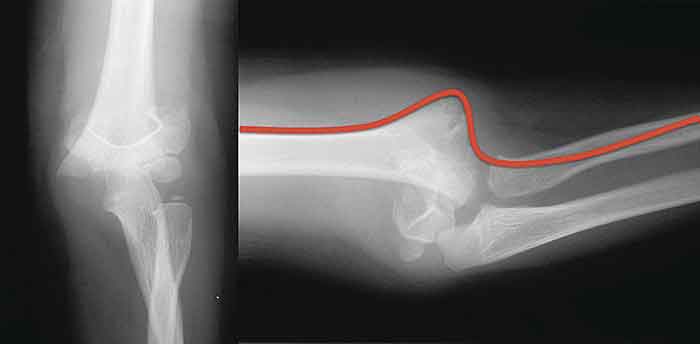

Avhoppad suprakondylär humerusfraktur (till vänster). Brachialis-artären rider över vass frakturände (till höger).

Reponerad och stiftad suprakondylär humerusfraktur (till vänster). Sidobild visar att kärlet nu har normalt förlopp (till höger) (jämför bilden ovan).